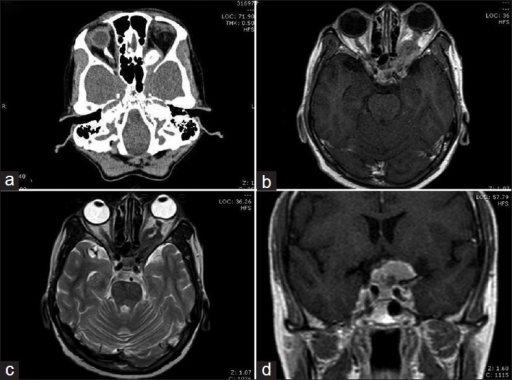

- MRI (조영 + fat suppression): "Tram-track sign" — 시신경 주위 선형 조영증강

- CT: 시신경초 석회화 (pneumosinus dilatans — 관련 소견)

- Tram-track sign ⭐⭐⭐: ONSM의 MRI 특징